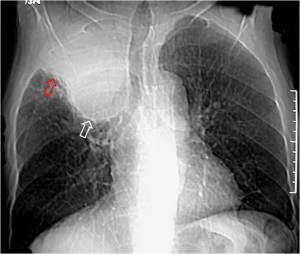

SIGNO DE LA ALTERACIÓN DEL CONTORNO AÓRTICO

La irregularidad, abombamiento o borramiento del arco aórtico en la radiografía de tórax en bipedestación o en decúbito supino, en un paciente con traumatismo torácico, obliga a descartar rotura aórtica como causa de dicha alteración. La flecha muestra el contorno aórtico anómalo. Además, hay un aumento de densidad en el hemitórax izquierdo correspondiente a derrame pleural –hemotórax en este caso-, que refuerza la sospecha de rotura aórtica.